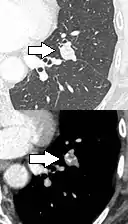

PET scan

If there is an intermediate risk of malignancy, further imaging with positron emission tomography (PET scan) is appropriate (if available). It can be done simultaneously as a CT scan in the form of PET-CT. Around 95% of patients with a malignant nodule will have an abnormal PET scan, while around 78% of patients with a benign nodule will look normal on PET (this is the test sensitivity and specificity).[15] Thus, an abnormal PET scan will reliably pick up cancer, but several other types of nodules (inflammatory or infectious, for example) will also show up on a PET scan. If the nodule has a diameter of less than one centimeter, PET scans are often avoided because of an increased risk of falsely normal results.[15][16][17] Cancerous lesions usually have a high metabolism on PET, as demonstrated by their high uptake of FDG (a radioactive sugar).

PET-CT of a tuberculoma.